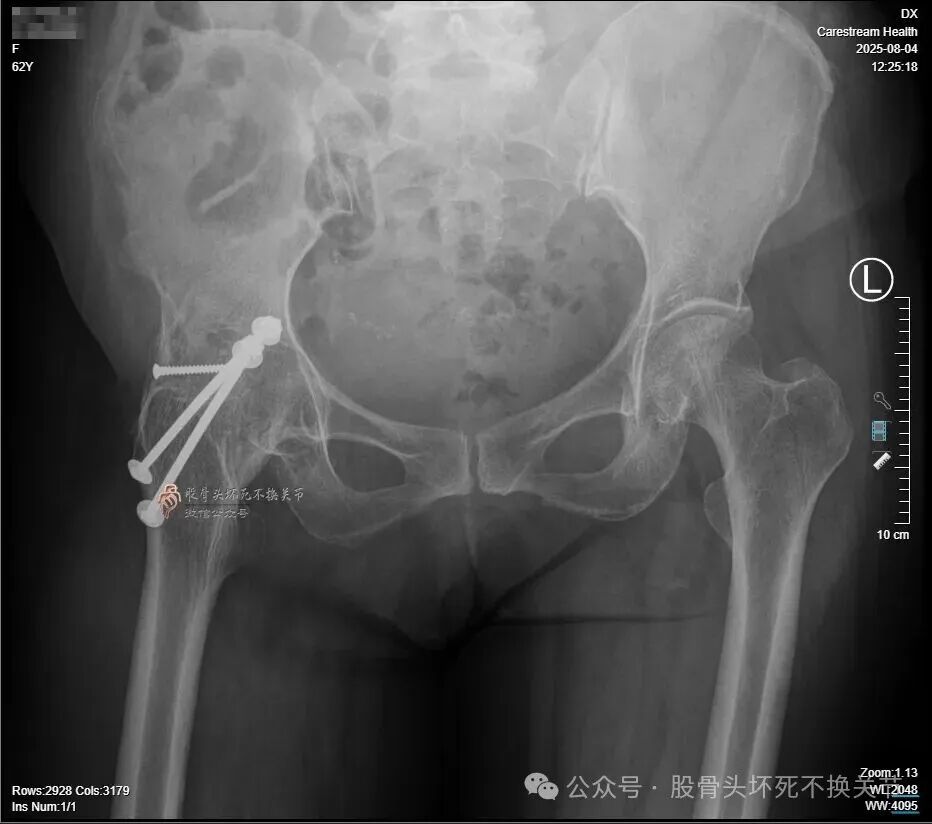

前段时间咱们提过一位62岁的病人,21年前因“右侧股骨头坏死”行右髋关节融合手术,近期要求行关节置换手术。在医生圈反响很大,现将结果汇报给如下。

髋关节骨性融合20余年,进行关节置换必须完全取出内固定,否则髋臼假体的安装就无法实现;残存内固定轻则影响假体安装,重则造成血管神经损伤,甚至危及生命。

之前采用的是金属螺栓固定,且螺母在髋臼内壁,所以不能存留任何内固定,即便取不出来,臼底就是开窗也要拿出来,但那样做无疑创伤非常大、危险也随之而来。

所以,摆在我们面前的第2个问题就来了——选择什么入路,才能做到创伤最小化?

虽然,取出内固定以后,可以改外侧、后路进行关节置换。

但是,我想强调的是,原切口(SP/变异DAA)不仅减小了创伤,更重要的是便于股骨颈截骨。

髋关节长期处于伸直外旋位,从后方进行股骨颈截骨空间狭小,一般需要先用窄骨刀打断股骨颈,再进行修整;髋关节前方入路则不同,切除关节囊之后,股骨颈广泛裸露于眼前,操作空间大,截骨轻而易举。

另外,因长期髋关节强直,髋周肌肉萎缩、韧带挛缩,假体复位牵引空间很有限,而前路置换较后路明显缩短了股骨头从髋臼外面滑入臼杯的距离,所以复位也更容易。